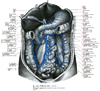

下行結腸【かこうけっちょう】 Retroperitoneal segment of the colon extending along the left side of the body between the splenic flexure and sigmoid colon.(下行結腸は左結腸曲から下行し、左腸骨窩においてS状結腸へ移行する。長さ25~30cmで、左結腸曲からほぼ垂直に下行し、左結腸窩でS状結腸に移行する。下行結腸は、上行結腸に比べて、細く、前方には大網・小腸があり、後方には左腎臓の外側縁・腰方形筋・腸骨筋・大腰筋が接する。上行結腸と同様腸間膜を欠き後腹壁に固定されている。下行結腸に沿って結腸傍溝が走る。とくに外側の傍溝は下方で骨盤腔に連なり、上方では横隔結腸ヒダで境される。)

Spalteholz

実習人体解剖図譜(浦 良治)